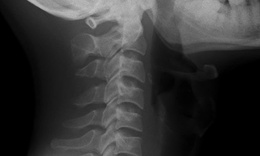

đau cổ vai gáy

Bài tập tốt cho người đau cổ vai gáy

Tra cứu bệnh - 12/04/2024 07:10SKĐS - Đau cổ vai gáy là tình trạng cơ của vùng cổ, vai, gáy bị co cứng gây ra. Bệnh liên quan đến hệ cơ xương khớp và mạch máu tại vùng vai gáy. Bên cạnh việc dùng thuốc, một số bài tập giúp cải thiện tình trạng này.